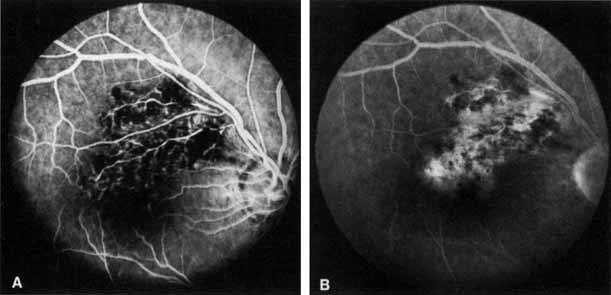

PATHOLOGY Occlusion of the central retinal vein is probably a result of both local and systemic causes. The actual mechanisms producing the clinical picture of central retinal vein occlusion may be roughly divided into those conditions that produce a physical blockage at the level of the lamina cribrosa, and those conditions in which hemodynamic factors result in an obstruction to the flow of blood. These mechanisms probably coexist in many patients with central retinal vein occlusion. The pathogenesis of this condition and the underlying histopathology have remained controversial ever since Michel1 first correlated the clinical appearance with the histopathology. The fact that relatively few eyes have been histopathologically examined during the freshly obstructed stage has contributed to the problem. Many of the reported cases have involved eyes that were enucleated because of long-standing neovascular glaucoma; secondary changes that did not play a role in the original occlusion may have occurred in these eyes. Histopathologic evaluation of eyes removed because of a central retinal vein occlusion demonstrates an occlusion at or just behind the level of the lamina cribrosa.2–7 At this location, certain anatomic factors predispose the central retinal vein to occlusion. First, the lumina of the central retinal artery and central retinal vein are narrower than they are in the orbital optic nerve, and the vessels are bound by a common adventitial sheath.8 Second, the lamina cribrosa is a sievelike, bisecting structure of connective tissue that not only provides support to the optic nerve, but also limits expansion and displacement of the optic nerve and the vessels within it. In 1878, Michel1 found a thrombus in one patient studied. Later, both Coats2 and Harms9 believed, based on their histopathologic findings, that a primary thrombus within the intraluminal portion of the central retinal vein was the most common cause of occlusion. Verhoeff,3 however, was an early advocate of the concept that endothelial cell proliferation was the primary obstructing mechanism, and he believed that thrombosis within the vein did not occur except in patients with sepsis. He believed that most cases diagnosed as thrombosis were actually dissecting aneurysms because he found the intimal lining forced away from the venous wall by the backup of blood in a tributary vein. Klein,5,6 who has done extensive clinical and pathologic studies of central retinal vein occlusion, believes that although primary thrombosis may occur, it is rare. She believes that thrombosis may occur more frequently as an end-stage phenomenon, complicating other initiating mechanisms in the obstructive process. Green and co-workers7 felt that the interval between occlusion and the time of histopathologic study must be considered when interpreting the histopathology of vein occlusion. They studied 29 eyes that were enucleated 6 hours to 10 years after occlusion. As a result of this study, they hypothesized that the flow of blood through the central retinal vein becomes increasingly turbulent as the vein progressively narrows at the lamina cribrosa, where it also may be further impinged on by arteriosclerosis of the adjacent central retinal artery. This turbulence damages the endothelium in the retrolaminar vein, which exposes collagen and initiates platelet aggregation and thrombosis.7,10 Their studies show the evolution of this thrombus. Initially, the thrombus adheres where the endothelium has been severely damaged. Endothelial cell proliferation and recanalization of the vein often occur as a reparative event. Inflammation manifesting itself as phlebitis, periphlebitis, or obliterating endophlebitis is a secondary late-onset factor. Years later, a thick-walled vein with a single channel may occur (phlebosclerosis).7 In some eyes an adjacent, partially obstructed, or narrowed central retinal artery has been observed. This observation is consistent with the prevailing clinical impression that the principal condition associated with retinal vein occlusion is arteriosclerosis. Because the central retinal artery is a true artery, it may be involved in the patchy disease of larger arteries (i.e., atherosclerosis). There is an increased incidence of generalized atheromatous disease in patients who have a central retinal vein occlusion.11,12 As part of this atheromatous change, sclerosis occurs in the common adventitia, which encircles both vessels within the rather rigid support structure of the lamina cribrosa. Compression or constriction of the vein lumen and changes within the vein wall, described as phlebosclerosis, occur. As mentioned, occlusion of the central retinal vein is also influenced by the anatomic confinement of the vein and the artery within the optic nerve, as well as the compactness of the lamina cribrosa and its surrounding connective tissue. Hayreh and co-workers13–16 have investigated the role of occlusion of the central retinal vein and central retinal artery in an animal model. They attempted to produce central retinal vein occlusion in healthy young monkeys by diathermy of the central retinal vessels in the orbit near their entry into the optic nerve sheath. Their study showed that occlusion in the orbit of the central retinal vein alone produced mildly engorged and tortuous vessels and a few retinal hemorrhages; all these conditions returned to normal in approximately 2 weeks. However, when both the central retinal vein and the central retinal artery in the orbit were obstructed simultaneously, a fundus appearance was produced that was “entirely characteristic” of central retinal vein occlusion.13 Later, histopathologic examination of these eyes showed a hemorrhagic infarct of the inner retinal layer. Hayreh and co-workers15 concluded from these experiments that concomitant arterial occlusion is essential in the production of an ischemic central retinal vein occlusion, although its occurrence is possibly only transient,16 and that the site of occlusion is important in determining both the severity and type of occlusion.16 However, this model of occlusion in the orbit of healthy young monkeys may not be comparable to the situation in the aging human, where the occlusion is located at or just posterior to the lamina cribrosa.379 Because fluorescein angiography does not typically show prolongation of arterial filling in central retinal vein occlusion, Fujino and associates17 investigated the role of arterial occlusion by producing central retinal vein occlusion in monkeys using an intravenous injection of neoprene. They were able to show that a primary and complete occlusion of the central retinal vein at the disc produces a secondary artery insufficiency. The ophthalmoscopic appearance produced in monkeys, however, is not identical to the appearance of central retinal vein occlusion in humans. This may be because this technique obstructs all the branch retinal vessels in the peripapillary region, which, in turn, may preclude collateralization.16 McLeod18 noted that in eyes with both a central retinal vein occlusion and a cilioretinal artery occlusion, there was a lack of retinal hemorrhages within the area of retina that was infarcted. He presented this an argument against the combined artery and vein occlusion hypothesis of Hayreh and colleagues.13–16 If an artery occlusion as well as a vein occlusion (combined occlusion) is necessary to produce the typical ophthalmoscopic picture of a central retinal vein occlusion, the retina should exhibit increased hemorrhage in the area supplied by the occluded cilioretinal artery. The histopathologic picture in venous occlusion is now considerably clearer as a result of a series of experiments on branch retinal vein occlusion in the monkey.19–21 This work shows that capillary nonperfusion (ischemia) can result after isolated venous outflow occlusion without the occurrence of primary arterial inflow occlusion (ischemic capillaropathy).22 Although these experiments were performed on branch retinal vein occlusions, there is every reason to believe that the ischemia of the retina seen in central retinal vein occlusion can result from venous outflow disease alone.23 Doppler ultrasound imaging has been used to examine the blood flow in the orbit, including the optic nerve head,24,25 and has been used to examine patients with central retinal vein occlusion.26–28,256,257 As might be expected, the venous velocity in the eye of a patient with central retinal vein occlusion is markedly reduced compared either with the unaffected eye or to control eyes.24,25 There is evidence, however, that the central retinal artery blood flow is also impaired in eyes with acute central retinal vein occlusion.28 In addition, vascular resistance is slightly higher in the ophthalmic artery and short posterior ciliary arteries of both the involved and the clinically healthy fellow eye of patients with central retinal vein occlusion compared with control eyes.28 There is also a trend toward higher vascular resistance of the central retinal artery in the clinically healthy eyes of patients with central retinal vein occlusion compared with control eyes.28 The retinal pathology in an ischemic central retinal vein occlusion consists of a hemorrhagic infarction of the retina that affects primarily the inner retinal layers.29 Neovascularization of the iris and anterior chamber angle can develop; less frequently, retinal neovascularization can also occur.10 This neovascularization is likely related to the unregulated expression of vascular endothelial growth factor (VEGF) in the cells of the neurosensory retinal when affected by the hypoxia in central retinal vein occlusion.329 Later changes include thickening of the retina and reactive gliosis.30 ETIOLOGY The precise etiology of central retinal vein occlusion is not entirely clear. There are now some clues as to the conditions associated with this condition. Many published articles have reported on the association between central retinal vein occlusion and some other condition, whether systemic or ocular. Although some of these associated conditions probably are, in some cases, related to central retinal vein occlusion, there is no way to determine in most cases whether the association is only coincidental on the basis of single-case reports. Any study that attempts to determine either the etiology of or the features associated with central retinal vein occlusion must be a large enough prospective study that it takes into account age- and sex-matched controls and includes a comprehensive, systemic evaluation. Some reports in the literature have been retrospective,31–33 others have had no control group,33–37,258,259,260 and some have not performed a prospective, systemic evaluation.31–34 We are aware of only one prospective, large study of risk factors for central retinal vein occlusion that includes an appropriate age- and sex-matched control group and a standardized, prospective, systemic evaluation.38 The Eye Disease Case-Control Study Group examined 258 cases of central retinal vein occlusion as well as 1,142 controls. An increased risk of central retinal vein occlusion was found in patients with systemic hypertension, diabetes mellitus, and open-angle glaucoma; the risk of central vein occlusion was decreased for patients with increasing levels of physical activity and increasing levels of alcohol consumption (Table 1). For women, the risk decreased with the use of postmenopausal estrogen and increased with a higher erythrocyte sedimentation rate. The authors did attempt to divide the cases into ischemic and nonischemic central retinal vein occlusion. The following conditions all showed a significant association with ischemic cases only: cardiovascular disease, electrocardiographic abnormalities, albumin-globulin ratio, α1-globulin, history of treatment for diabetes mellitus, and blood glucose level. Both systolic and diastolic blood pressure showed significant associations with both types of central retinal vein occlusion, but the odds ratio is greater for the central retinal vein occlusion. Overall, a stronger cardiovascular risk profile was shown for the ischemic type of central retinal vein occlusion.

The prognosis for ischemic central retinal vein occlusion is generally poor because of decreased visual acuity and neovascularization. Visual loss occurs because of macular edema, capillary nonperfusion, overlying hemorrhage (either retinal or vitreal), or a combination of all these. Retinal edema usually gradually subsides except in the macula, where it may persist for many months or years. Macular holes or cysts may form.83,84 Pigment clumping or fine pigment stippling and pigment atrophy are not uncommon, and persistent macular hemorrhage, even years after the occlusion, has been noted.83 Hard exudates often form an irregular circinate configuration around the macula and become more prominent months later. Occasionally an epiretinal membrane may form. In the chronic phase, most hemorrhages gradually disappear over many months; however, scattered, flame-shaped hemorrhages and dot hemorrhages, particularly in the periphery, may be seen for years. Cotton-wool patches and microaneurysms likewise tend to disappear after several months, although in some cases the latter may persist. The venous tree becomes less tortuous and dilated. Prominent venous loops, which are collateral communications, may be observed on the surface of the disc (Fig. 6).85 These loops develop within 3 to 14 months after occlusion from the existing retinal vasculature and are collateral vessels between the obstructed disc capillaries and the unobstructed choroidal or pial capillaries.323 These retinochoroidal collateral veins, if they develop, may protect against anterior segment neovascularization,328 but may not be associated with a better visual prognosis.105 Collaterals between the central retinal vein within the globe and the patent central retinal vein behind the occlusion have not been observed.86 The extent and speed of retinal recovery probably depends to some degree on how quickly collateral vessels form, how rapidly recanalization occurs, and how adequately these compensatory mechanisms restore normal outflow. However, the exact nature and course of the collateral vessels are disputed. Anastomotic channels may develop within the retinal vasculature if pressure differentials develop between its major venous trunks. Changes in the retinal arterioles include both segmental and generalized narrowing as well as sclerosis, which is evidenced by both sheathing and widening of the light reflex. Sheathing of the veins is also common. The disc may appear nearly normal except for sheathing of the vessels in and around the papilla, and some blurring of the margins may persist. Sometimes optic atrophy is present. The fluorescein angiographic appearance varies greatly, depending on the extent of recovery. All the findings in the acute phase, consisting of venous and capillary engorgement, microaneurysms, staining of the veins, patchy extravascular fluorescence, and capillary nonperfusion, may persist indefinitely. In most instances, these findings eventually diminish so that few significant features are present on the angiogram; collateral vessels, if present, may be the only pathognomonic feature. The most serious complication of central retinal vein occlusion is neovascularization (Table 2). Neovascularization elsewhere (NVE) occurs less frequently than neovascularization of the iris (NVI), and usually only in ischemic occlusions.66 The low incidence of retinal surface neovascularization in ischemic central retinal vein occlusion is thought to be due to the destruction of endothelial cells, which provide the source for endothelial proliferation and neovascularization.87